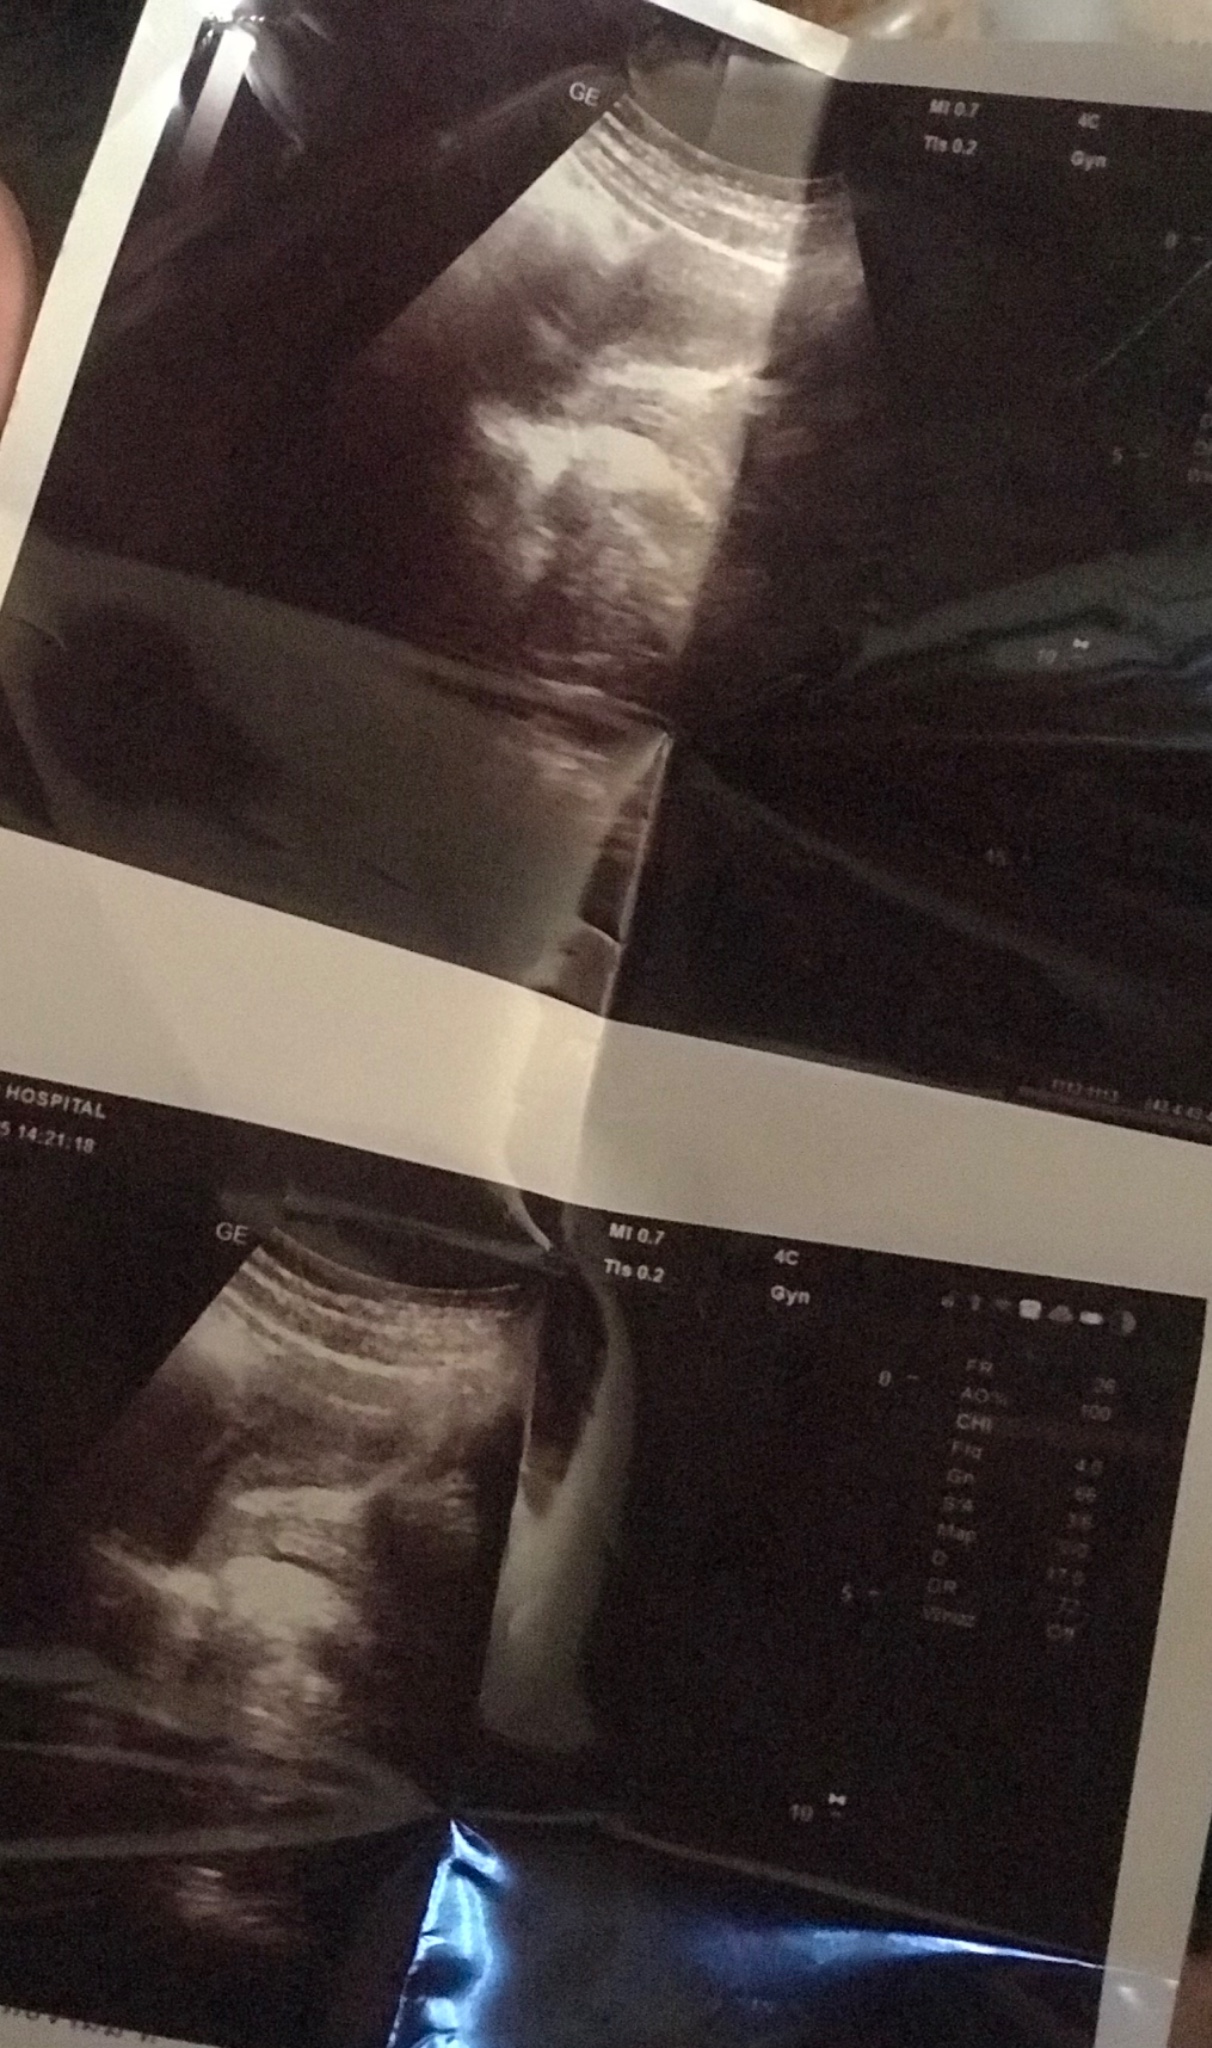

อัลตราซาวด์แล้วเป็นแบบนี้คืออะไรคะ?

คือเราไปอัลตราซาวด์ค่ะแล้วขึ้นแบบนี้คือยังไงคะตรงขาวๆคืออะไรหรอคะหมอไม่บอะไรเลยแค่บอกว่าไม่มีไร เรากินยาคุมปรับฮอร์โมนต์แล้วมีอะไรกับแฟนแบบปล่อยใน มีเลือดออกเราจึงไปหาหมอ